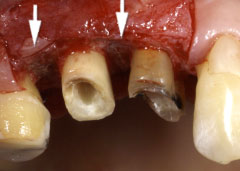

| 歯周病が進行したケースでは盲目下でポケット内の歯石を確実に除去するには限界があります。 | 局所麻酔をした後、歯茎を切開し、明視下にて歯根面の歯石や炎症組織を取り除き、歯周ポケットの除去をおこないました。 |

| 深い虫歯のケースでは、切除療法を行い虫歯を取り除き、健全な歯質を歯肉の上に出し、歯肉の盛り上がりを数ヶ月待ってから歯型をとります。 |

| 一見分りませんが、かなり歯周病が進行していました。歯周ポケットの改善や歯槽骨を平坦にして清掃しやすい環境を整えます。数ヶ月、歯肉の盛り上がりを待ってから適合の良いクラウンを被せます。 | ||